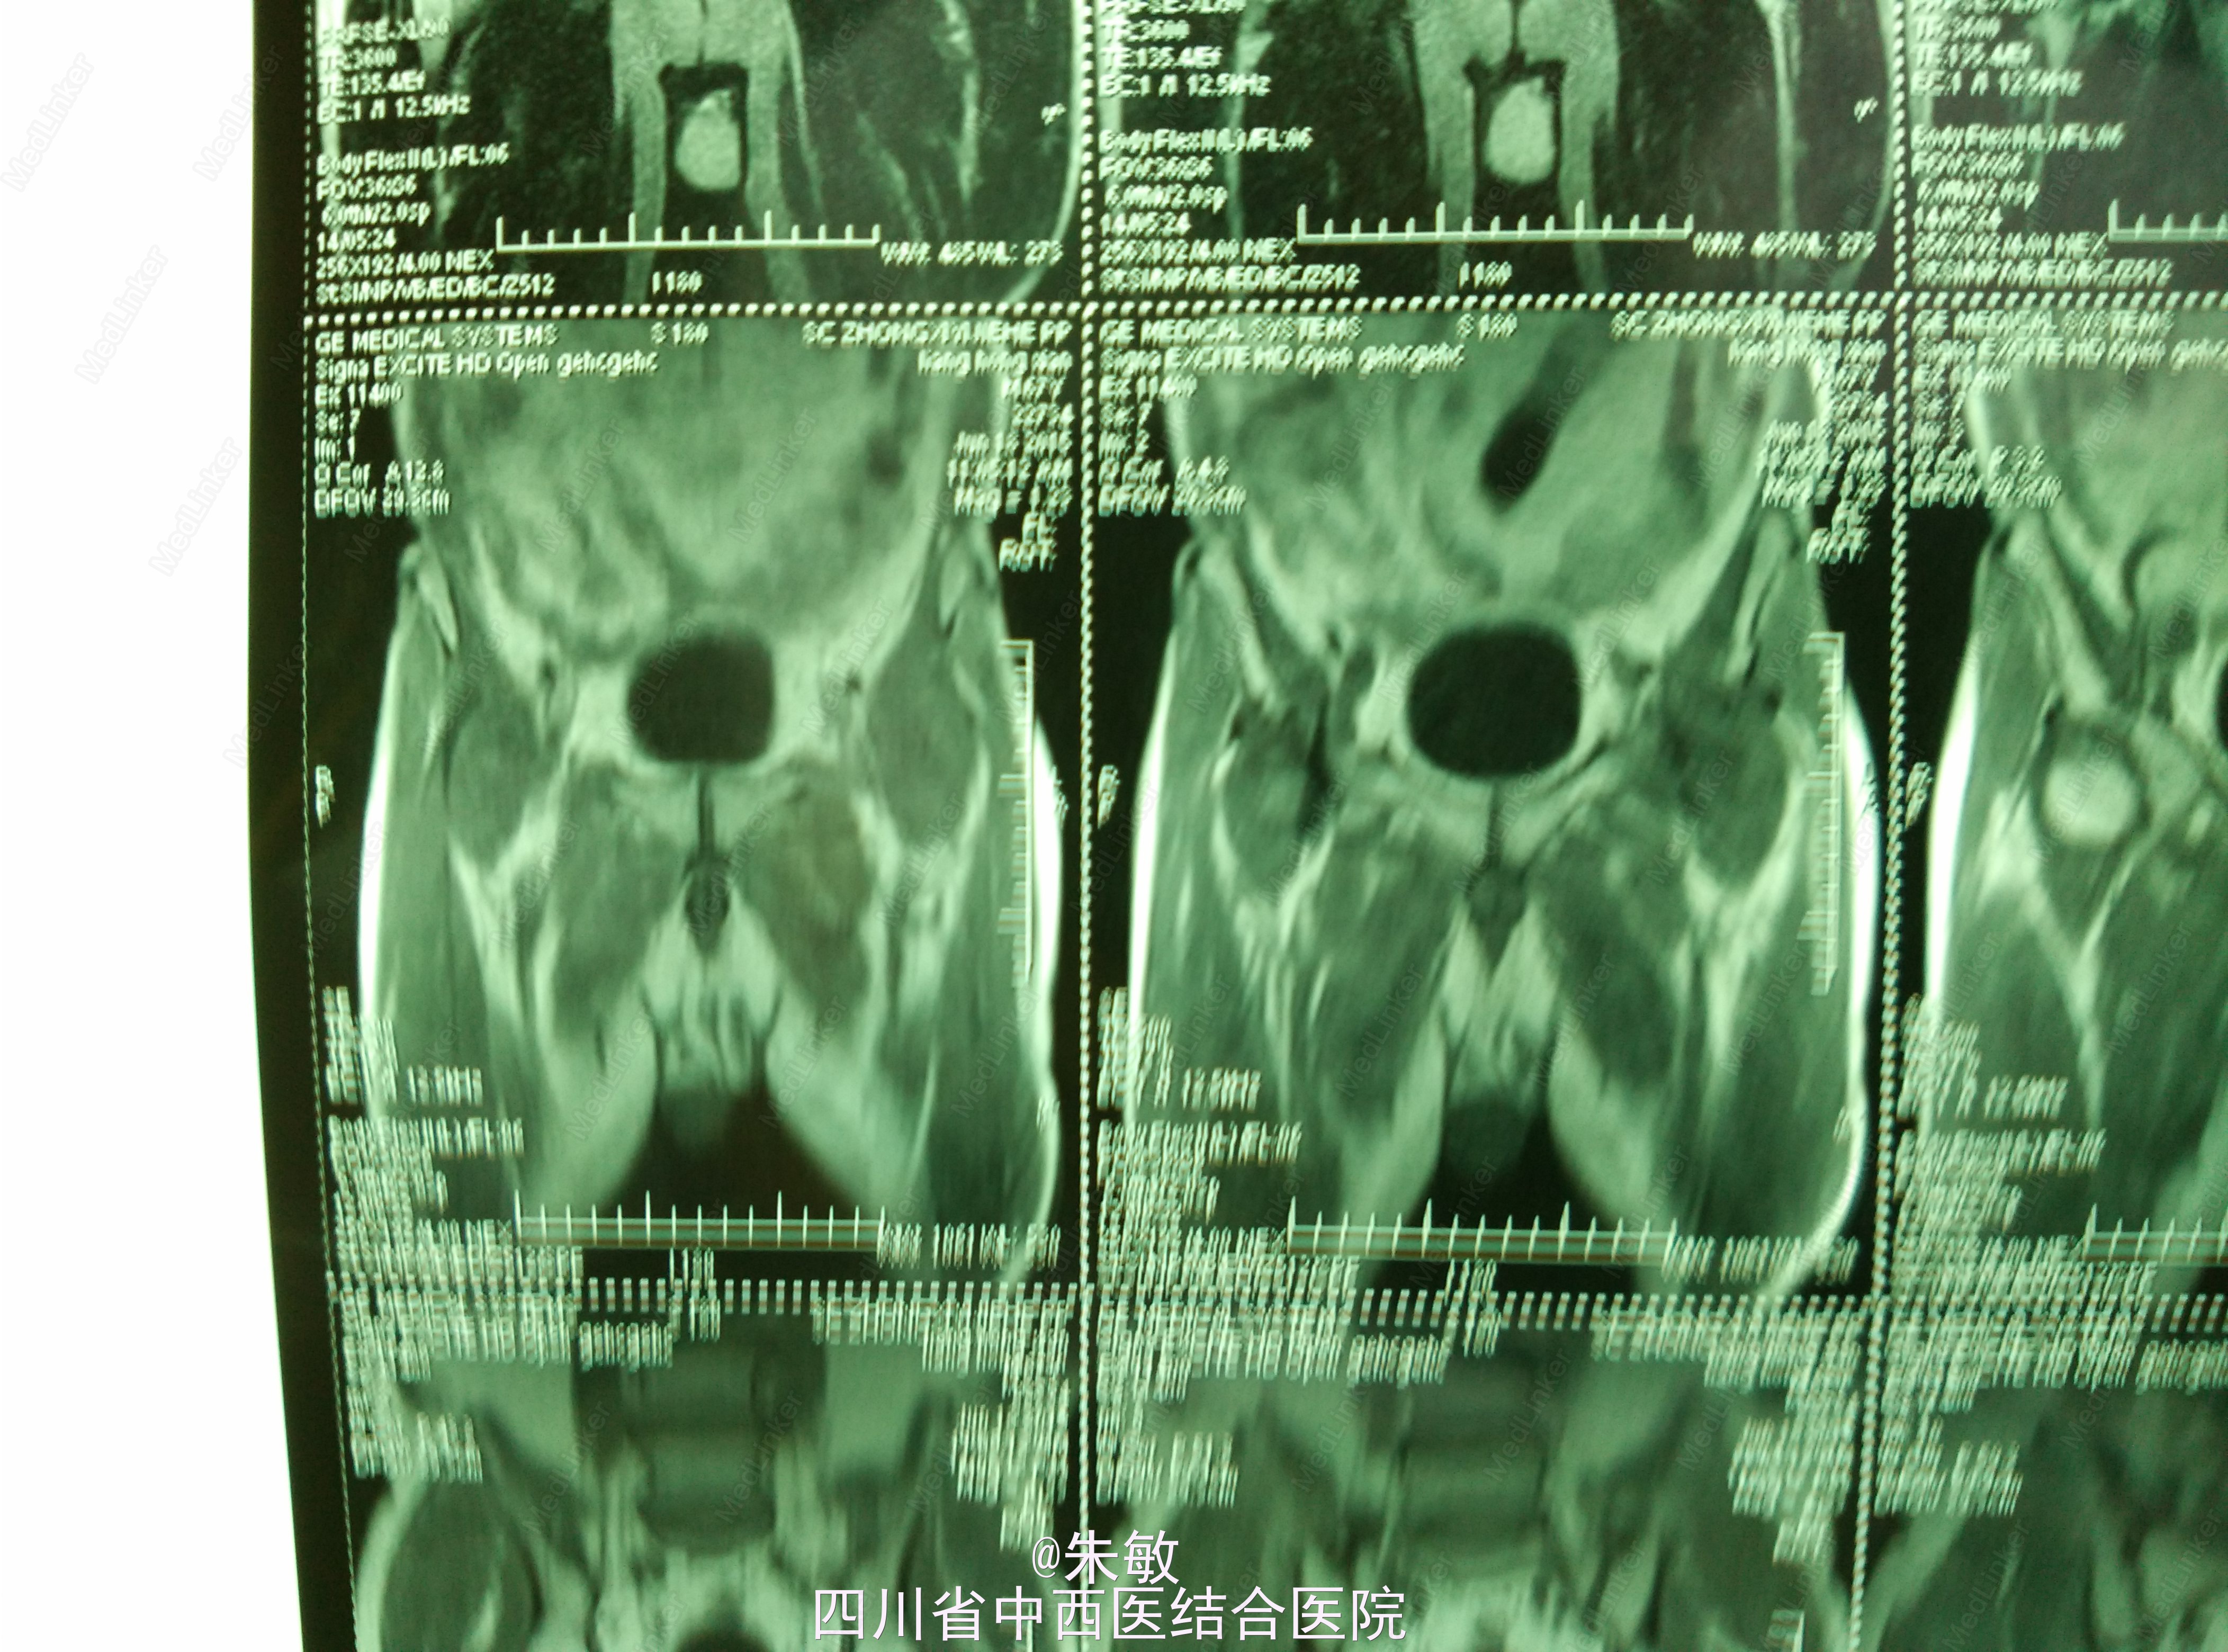

4.本院MRI:左髋关节间隙稍窄,两侧股骨头关节面下斑片、条状异常信号,两侧髋关节囊积液,以左侧明显。关节周围软组织层次清楚,考虑双侧股骨头无菌坏死。

诊断: 双侧股骨头坏死